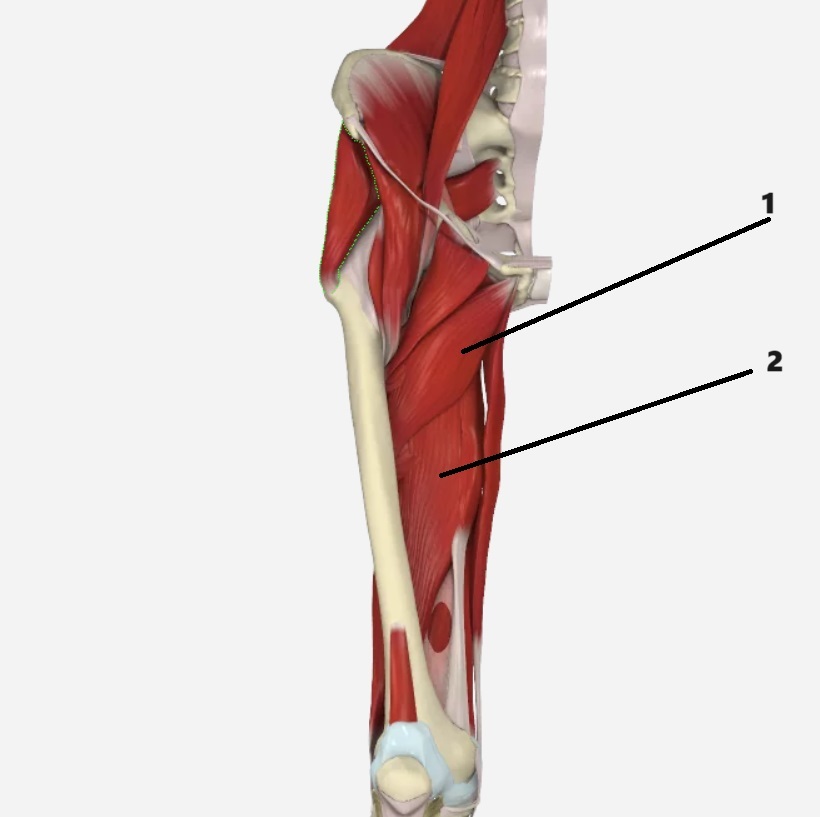

1

adductor brevis

2

adductor magnus